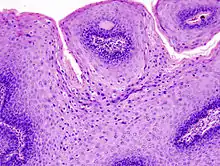

The diagnosis of genital warts is most often made visually, but may require confirmation by biopsy in some cases.[19] Smaller warts may occasionally be confused with molluscum contagiosum.[18] Genital warts, histopathologically, characteristically rise above the skin surface due to enlargement of the dermal papillae, have parakeratosis and the characteristic nuclear changes typical of HPV infections (nuclear enlargement with perinuclear clearing). DNA tests are available for diagnosis of high-risk HPV infections. Because genital warts are caused by low-risk HPV types, DNA tests cannot be used for diagnosis of genital warts or other low-risk HPV infections.[4]